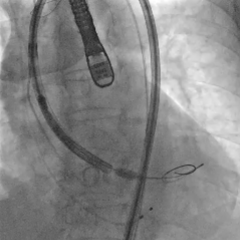

根部造影,瓣叶活动差

20mm球囊预扩,微腰微漏

输送器过弓

snare辅助下跨瓣

瓣膜初始定位

第一次释放,瓣膜位置偏高,选择回收